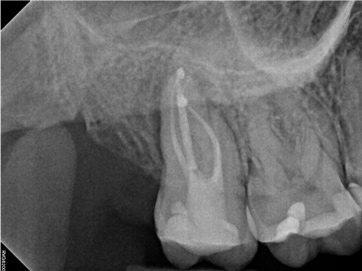

In the first case study, a young female patient was told she had a tooth (tooth No. 2, Figure 3) that should be extracted due to extensive bone loss. Using CBCT, the clinician was able to identify a large lateral canal within the palatal root. Despite the bone loss, the patient was eager to save her tooth. He offered to treat the tooth with the broad-spectrum acoustic technology. As shown in Figure 4, the preparation space was much smaller, which he was able to obturate efficiently. In addition, the small pinpoint of sealer in the middle of the palatal root indicated that the palatal lateral canal had been addressed (Figure 5). In the clinician's opinion, this area was likely the primary source of much of the bone loss.

Figure 6 through Figure 8 demonstrate that, 5 months after the procedure, complete healing had occurred, notably on the distal, where the probing had resolved to 2 mm. The patient then had a crown placed by her general dentist. Given her positive experience with the technology, she was eager to return as needed for continued follow-up.

Fig 4. Case 1: CBCT showed a large lateral canal within the palatal root (Fig 3). There was a small preparation space, which was efficiently obturated (Fig 4). A small pinpoint of sealer in the middle of the palatal root indicated that the palatal lateral canal had been addressed (Fig 5). After 5 months, CBCT demonstrated complete healing (Fig 6), notably on the distal, where probing had resolved to 2 mm. Radiographic images were taken immediately postoperatively (Fig 7) and 5 months postoperatively (Fig 8).

Fig 5. Case 1: CBCT showed a large lateral canal within the palatal root (Fig 3). There was a small preparation space, which was efficiently obturated (Fig 4). A small pinpoint of sealer in the middle of the palatal root indicated that the palatal lateral canal had been addressed (Fig 5). After 5 months, CBCT demonstrated complete healing (Fig 6), notably on the distal, where probing had resolved to 2 mm. Radiographic images were taken immediately postoperatively (Fig 7) and 5 months postoperatively (Fig 8).

Fig 6. Case 1: CBCT showed a large lateral canal within the palatal root (Fig 3). There was a small preparation space, which was efficiently obturated (Fig 4). A small pinpoint of sealer in the middle of the palatal root indicated that the palatal lateral canal had been addressed (Fig 5). After 5 months, CBCT demonstrated complete healing (Fig 6), notably on the distal, where probing had resolved to 2 mm. Radiographic images were taken immediately postoperatively (Fig 7) and 5 months postoperatively (Fig 8).

Fig 7. Case 1: CBCT showed a large lateral canal within the palatal root (Fig 3). There was a small preparation space, which was efficiently obturated (Fig 4). A small pinpoint of sealer in the middle of the palatal root indicated that the palatal lateral canal had been addressed (Fig 5). After 5 months, CBCT demonstrated complete healing (Fig 6), notably on the distal, where probing had resolved to 2 mm. Radiographic images were taken immediately postoperatively (Fig 7) and 5 months postoperatively (Fig 8).

Fig 8. Case 1: CBCT showed a large lateral canal within the palatal root (Fig 3). There was a small preparation space, which was efficiently obturated (Fig 4). A small pinpoint of sealer in the middle of the palatal root indicated that the palatal lateral canal had been addressed (Fig 5). After 5 months, CBCT demonstrated complete healing (Fig 6), notably on the distal, where probing had resolved to 2 mm. Radiographic images were taken immediately postoperatively (Fig 7) and 5 months postoperatively (Fig 8).